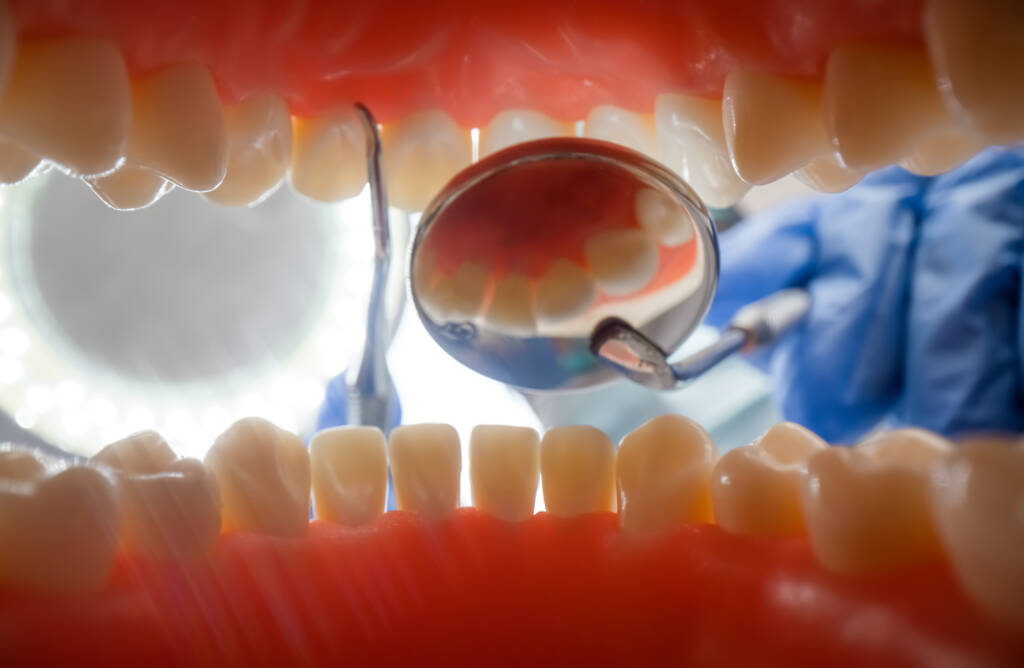

Diş taşı, diş eti çizgisinin hem üzerinde hem de altında birikerek zamanla diş eti iltihabına ve periodontitis (diş eti hastalığı) gibi daha ciddi sorunlara zemin hazırlar. Profesyonel temizlik sırasında ultrasonik cihazlar ve el aletleri kombinasyonuyla diş taşı titizlikle uzaklaştırılır.

Temizlik sonrasında dişlerin yüzeyine uygulanan polisaj işlemi, mine yüzeyini pürüzsüzleştirir ve yeni plak oluşumunu geciktirir. Bu işlem aynı zamanda dişlerde belirgin bir parlaklık ve ferahlık hissi yaratır. Tüm süreç konforlu ve ağrısız biçimde tamamlanır.

Profesyonel temizlik yalnızca fiziksel bir müdahale değildir; aynı zamanda ağız sağlığının genel bir değerlendirmesidir. Temizlik sırasında diş eti sağlığı, cep derinlikleri ve varsa erken dönem çürük belirtileri de gözlemlenir. Gerekirse ek tedavi önerileri sunulur.